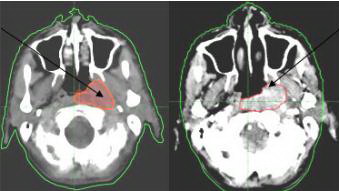

4. Một số kết quả điều trị

Hình ảnh trước và sau

xa_phau_6.jpg